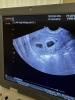

Девочки, покажите узи в 6 недель диди беременности. До четверга не доживу от переливаний. Одно пя 12 мм, есть эмбрион и сердце, а второй 4 мм, сердца нет, но эмбрион есть 1 мм. Слишком большая разница?

В 5н и 5дн было два пя по 11-13мм, два эмбриона, один 2,8 а другой 3,2 и у обоих СБ+

Но у меня эко, у них возраст отличался на 1 день, при естественной беременности может быть больше разница